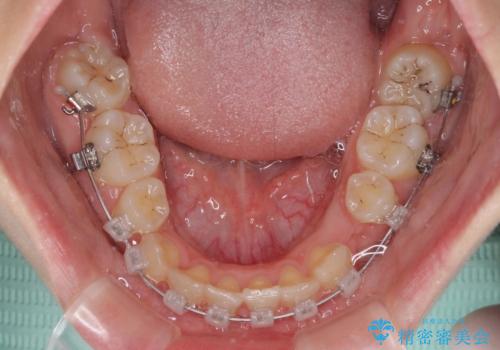

重度叢生と埋もれた奥歯 8本を抜歯したワイヤー矯正

親知らずの抜歯により埋もれた奥歯周辺の歯肉が切除され、矯正装置が装着できるようになりました。

奥歯の移動、特に下顎大臼歯の移動は時間がかかることが多く、3年以上の治療期間を想定していましたが、想像以上に動きがよく、2年強で終えることができました。